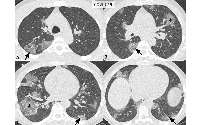

RSNA Publishes Fleischner Statement on Chest Imaging and COVID-19

A multinational consensus statement from the Fleischner Society on the role of chest imaging in the management of patients with COVID-19 was jointly published in Radiology and Chest.

RSNA Publishes Expert Consensus on COVID-19 Reporting

RSNA has published an expert consensus statement on reporting chest CT finding related to COVID-19. The statement, published in Radiology: Cardiothroacic Imaging, is endorsed by the RSNA, the American College of Radiology and the Society of Thoracic Radiology.